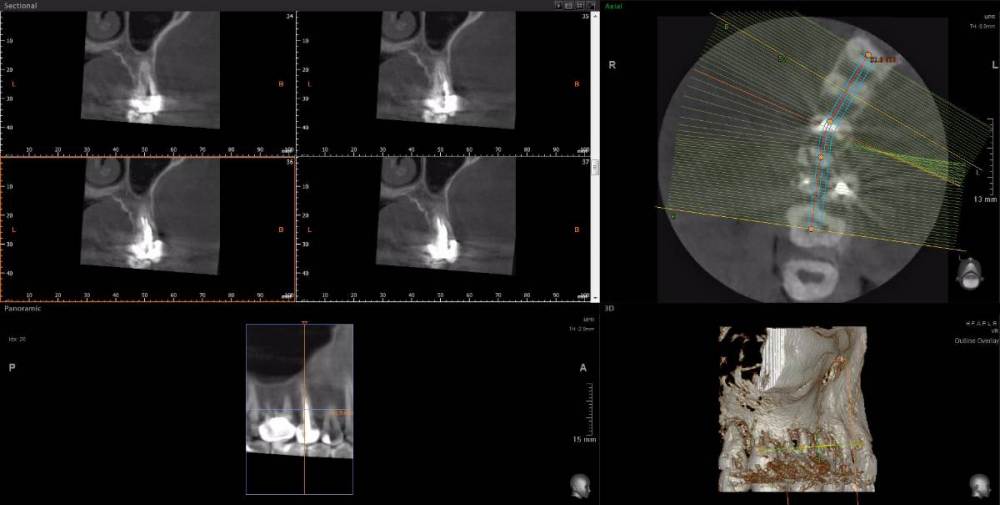

Рабин Опубликовано 18 мая, 2021 Автор Поделиться Опубликовано 18 мая, 2021 Добрый день! Сделала КТ этого зуба, как вы просили... https://cloud.mail.ru/stock/kkbze24nzBzfEqnUbdPwtsei Видите ли вы воспаление на нём и можно ли его спасти? Интересует также соседний 15 зуб. Спасибо! Ссылка на комментарий

wladdX Опубликовано 18 мая, 2021 Поделиться Опубликовано 18 мая, 2021 (изменено) Зуб 16, на мой взгляд, придётся удалить. Зуб 18 тоже Зуб 15 вроде бы и не вызывает особых восторгов, но и явного неприятия тоже. Изменено 18 мая, 2021 пользователем wladdX 2 Ссылка на комментарий

red_butler Опубликовано 20 мая, 2021 Поделиться Опубликовано 20 мая, 2021 18.05.2021 в 23:24, wladdX сказал: Зуб 16, на мой взгляд, придётся удалить. +1 Ссылка на комментарий

wladdX Опубликовано 29 мая, 2021 Поделиться Опубликовано 29 мая, 2021 18 - там приличных размеров корневая гранулёма, излечить нереально 1 Ссылка на комментарий